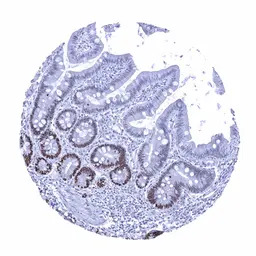

IHC-P analysis of human duodenum mucosa tissue section using GTX04459 SOX9 antibody [MSVA-709R] HistoMAX.